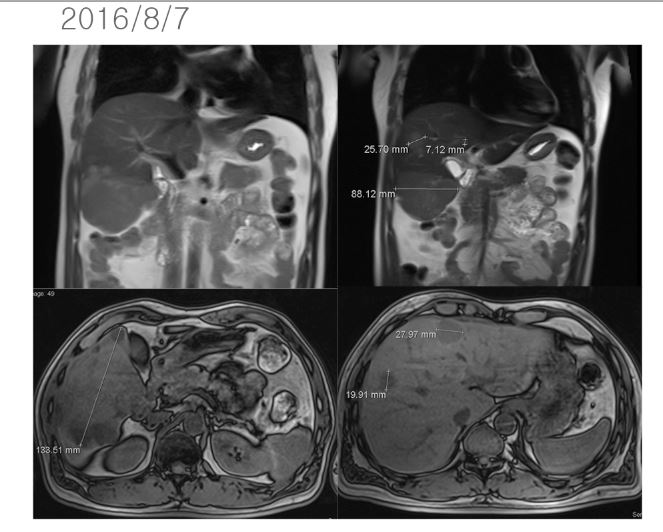

47세의 남자인 이 환자는 젊어서부터 담배를 피기 시작하였는데 20년간 거의 하루 한 갑이상을 피웠고 최근에 경제사정이 나빠지자 스트레스로 하루 2 갑씩을 피웠다고 한다. 그런지 1년이 되어서  복통을 느껴서 검진 결과 간암(hepatocellular carcinoma)으로 복부에 임파전이가 있고 여러 개의 작은 암덩이와 함께 제일 큰 간암의 크기는 약 11cm 정도로 판명되었다(2016/7/9).

이후 8월 7일 MR상 거의 간의 우엽에 14cm 가까이 되는 종양이 보이는데 그 사이에 암이 3cm 이상 자랐다는 이야기가 된다. 이후 K 의료원에서 넥사바라고 불리우는 sorafenib을 2달 동안 사용하였다. 이후 결과는 간의 종양은 약간 자랐다고 볼수 있고 간암의 수치는 많이 떨어졌다고 하였다.